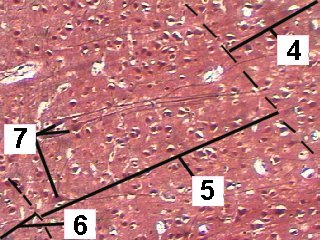

A very low magnification of the cerebrum demonstrating the different layers.

The cortex consists of 6 weakly differentiated layers.